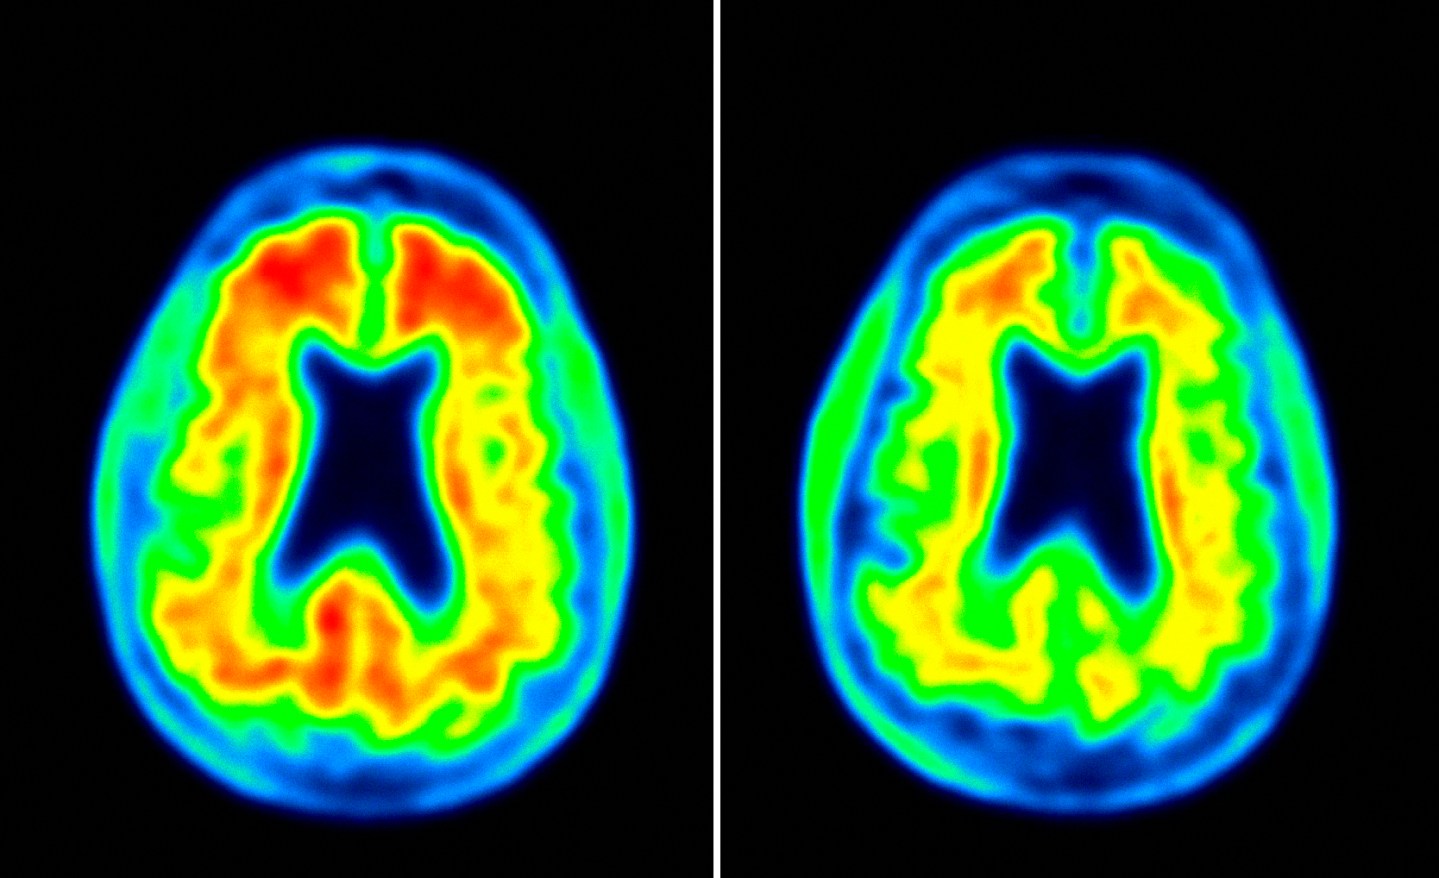

There are a number of issues to consider with BAN2401. For one thing, it only appeared to slow down Alzheimer’s patients’ decline in those at an earlier stage of the disease. Furthermore, the treatment focuses on battling the buildup of a protein called beta amyloid in the brain, part of a strategy dubbed the “amyloid hypothesis.”

This hypothesis has been at the core of many Alzheimer’s drug development efforts which have ultimately ended in heart break, including for companies like Eli Lilly, Merck, Roche, and other pharmaceutical giants. But Biogen has essentially gone all in on targeting amyloid — another one of its experimental Alzheimer’s medicines, aducanumab, is an amyloid antibody in late-stage trials.